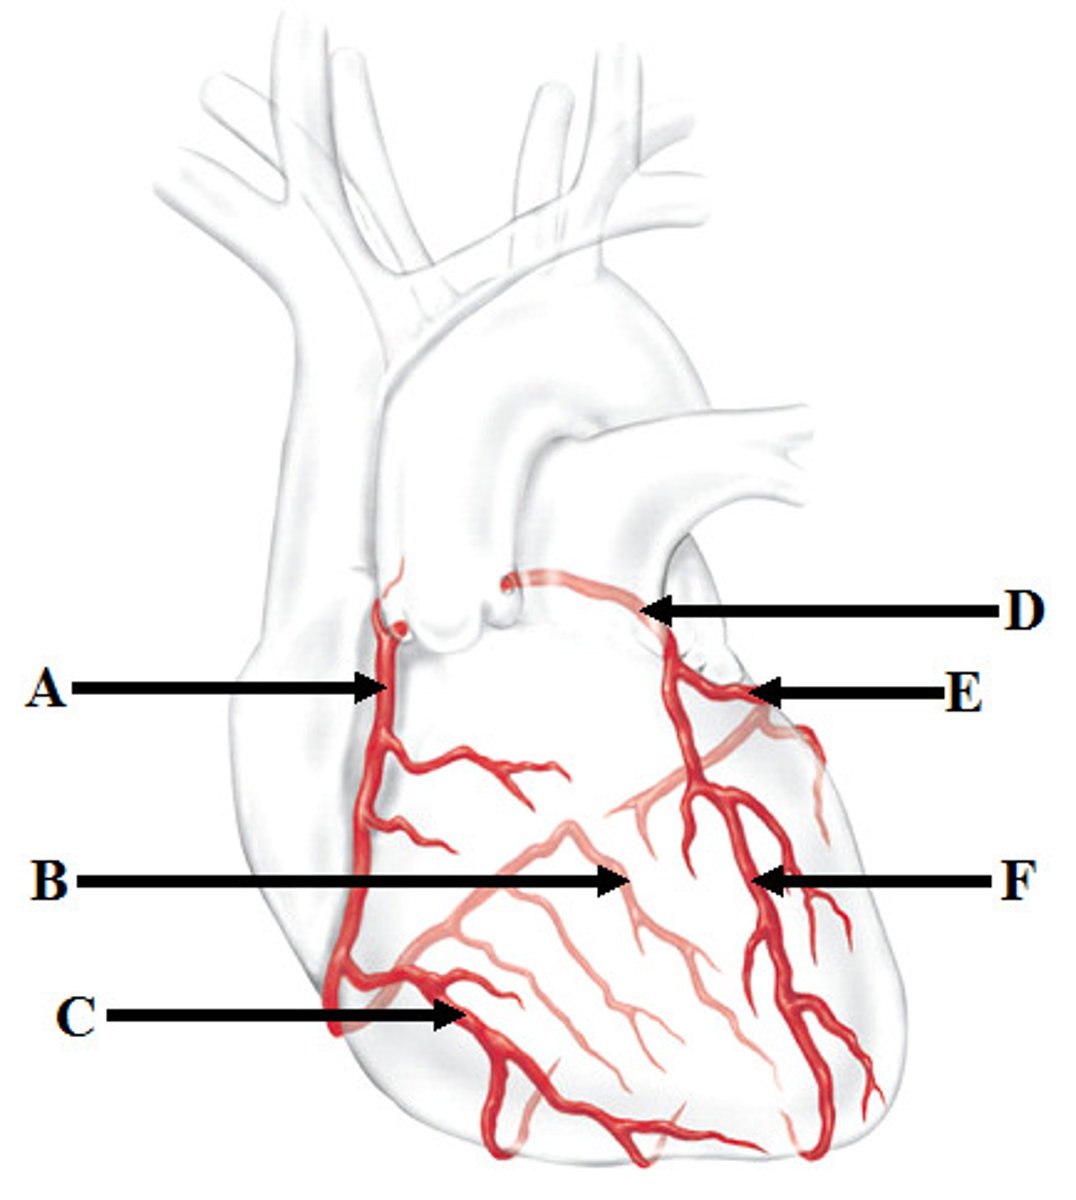

Coronary arteries (right (A) and left(D))

Marginal artery (C) and Posterior Interventricular artery (B)

Branches of right coronary artery

Anterior Interventricular artery (F) and Circumflex artery (E)

Branches of the left coronary artery